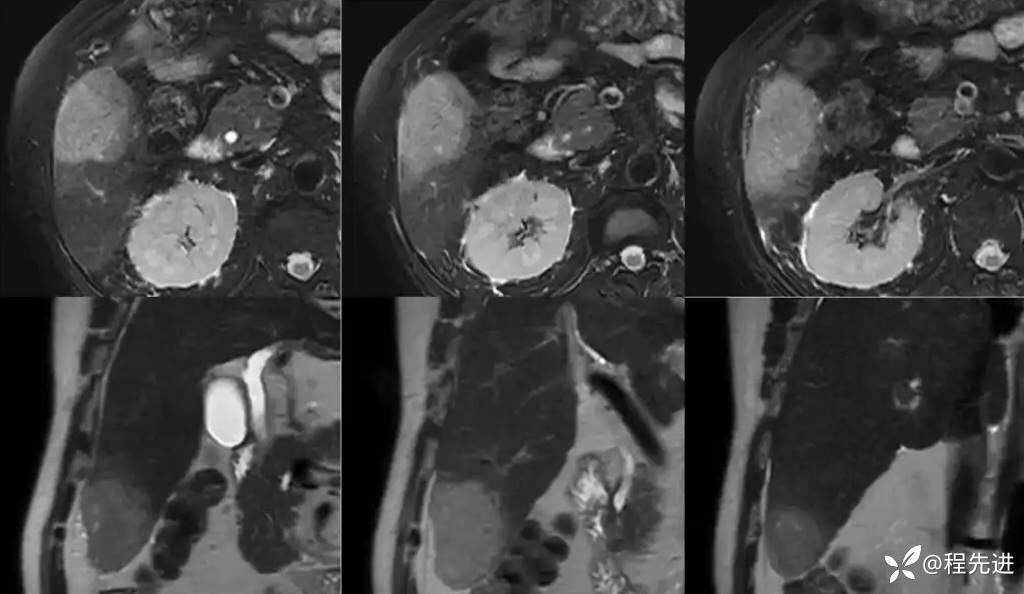

T1同反相位:

T2:

DWI、ADC

T1蒙片:

动脉期:

门静脉期: